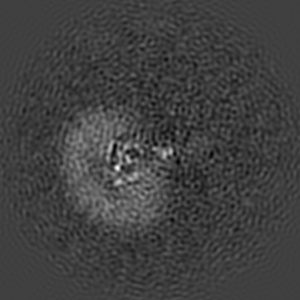

Cryo-EM structure of human GABA(B) receptor bound to the positive allosteric modulator rac-BHFF

Sample: Gamma-aminobutyric acid type B receptor

Fitted models: 7ca3